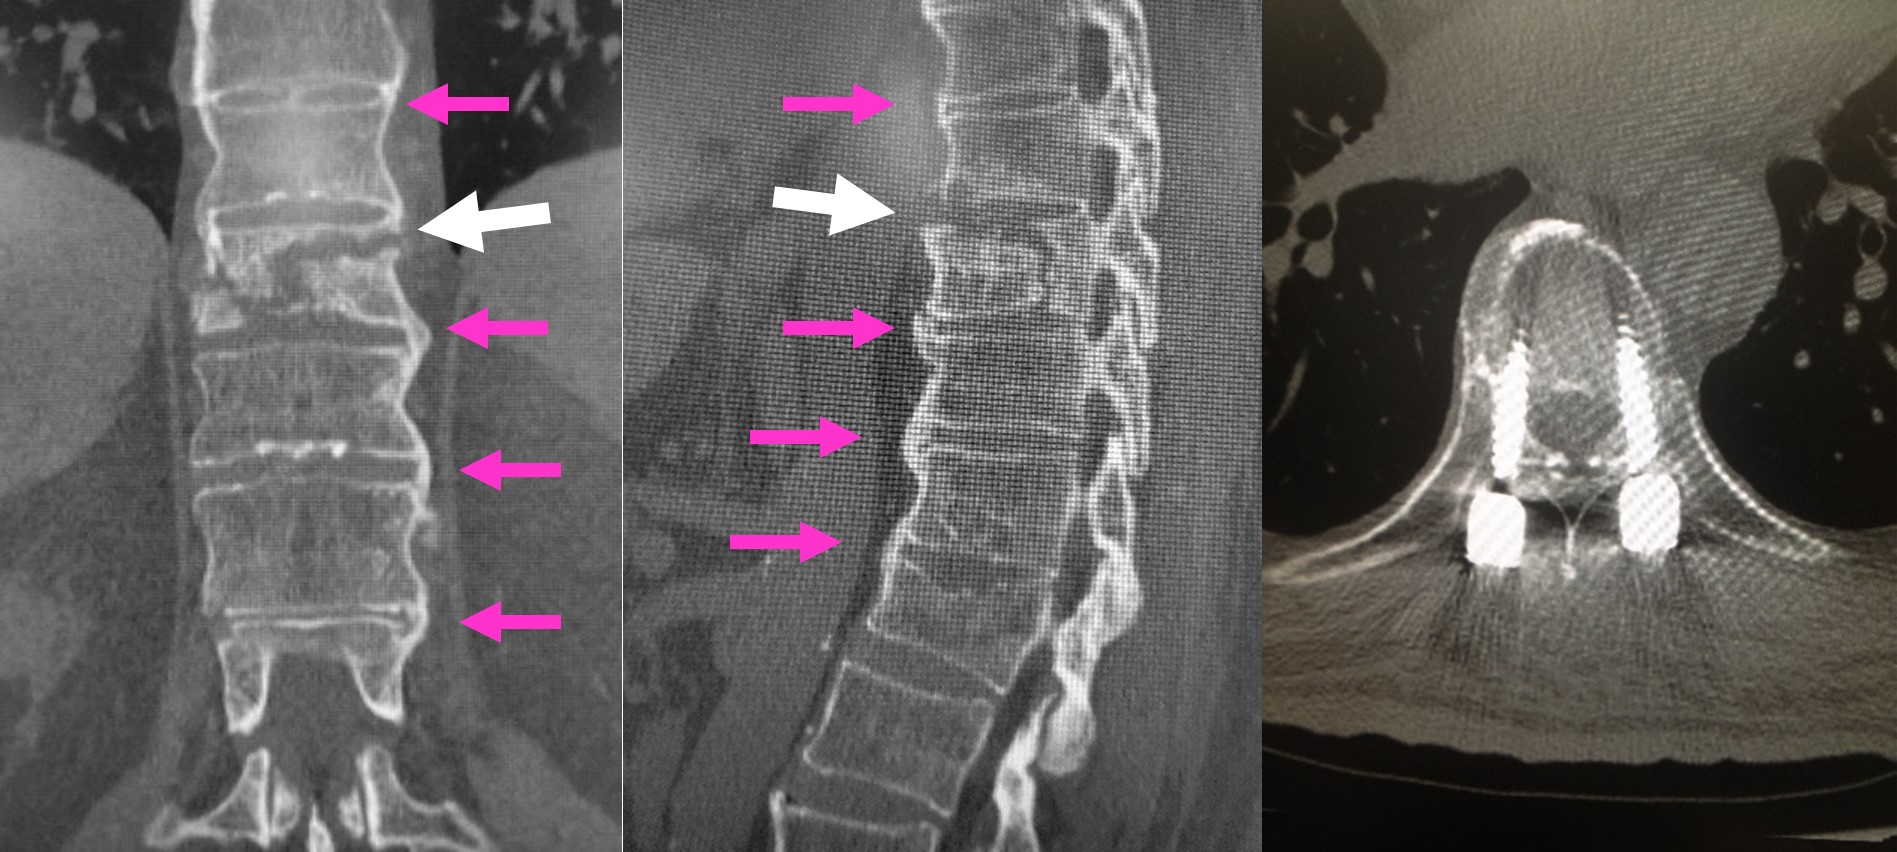

図 DISHのCT画像

(左、まん中)DISHで骨癒合(ピンク矢印)をしていましたが、転落で一部骨折を生じています(白矢印)。

(右)すぐにボルトで背骨を固定して、背骨が安定しました。